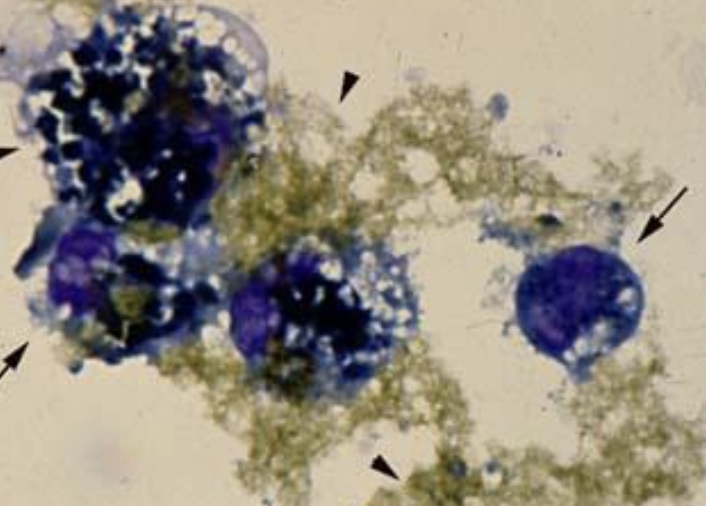

what does the image show?

intercellular bile lakes showing accumulation of bile in canaliculi

hepatocellular carcinoma